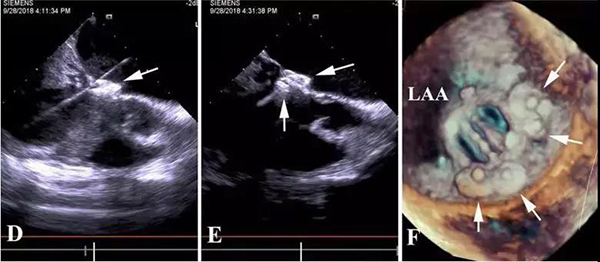

患者冯某,年仅44岁,她的治疗颇更具曲折性和借鉴性。二尖瓣置换术后4月,体质弱,发现两处MPVL,分别位于7点和1 点处,漏口大,呈不规则形。首次瓣周漏封堵采取经右胸小切口途径,顺利植入两枚封堵器。

然而,封堵器释放后,发现封堵器伞间残余漏(宽仅2mm),就是说“铆钉”的缝隙里仍有血漏过。高速通过缝隙的血流受剪切力影响,造成血细胞破坏,患者术后严重溶血、贫血和血红蛋白尿,白细胞高,血小板低,肝肾功能降低,黄疸,需要间断输血维持。

怎么办?再次开胸体外循环手术患者难以耐受,可能意味着死亡,风险更大。而再次经胸封堵术需要去堵“铆钉”间的缝隙,漏口小,对医生的难度大、风险大。有导丝无法通过漏口、捅掉以前植入的封堵器,术后仍然有残余漏、溶血等风险。顶着巨大的压力,李红昕和郭文彬带领的医疗团队经过认真的讨论、分析,决定依据心尖入路比较直的特点,改经左胸-心尖途径去封堵“铆钉”间的缝隙。术中,他们利用自主发明的直中空探条输送系统,成功将导丝送过两个伞盘的间隙,分别再次植入一枚特质封堵器,共4枚,完全封堵住了MPVL。术后患者血红蛋白尿、贫血、黄疸消失,肝肾功能恢复正常,痊愈出院。